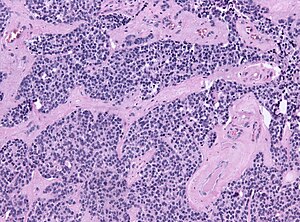

Features:[1]

- Small round (blue) cell tumour with:

- Stippled chromatin.

- High NC ratio.

- +/-Flexner-Wintersteiner rosette - rosette with empty centre (donut hole).

- +/-Fibrillary, eosinophilic material (neuropil-like).[2]

Images: